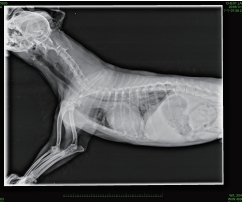

目前治療仍大多採內科持續服用藥物方式延緩病情發展,並定期回診藉由聽診,量測血壓,追蹤腎指數,胸腔X光以及心臟超音波來監控病情已獲得良好生活品質。

經由心臟超音波,胸腔X光,血壓,及血液檢查完整評估病犬心臟病分級。並依照其心臟病分期,給予所需的藥物及治療。